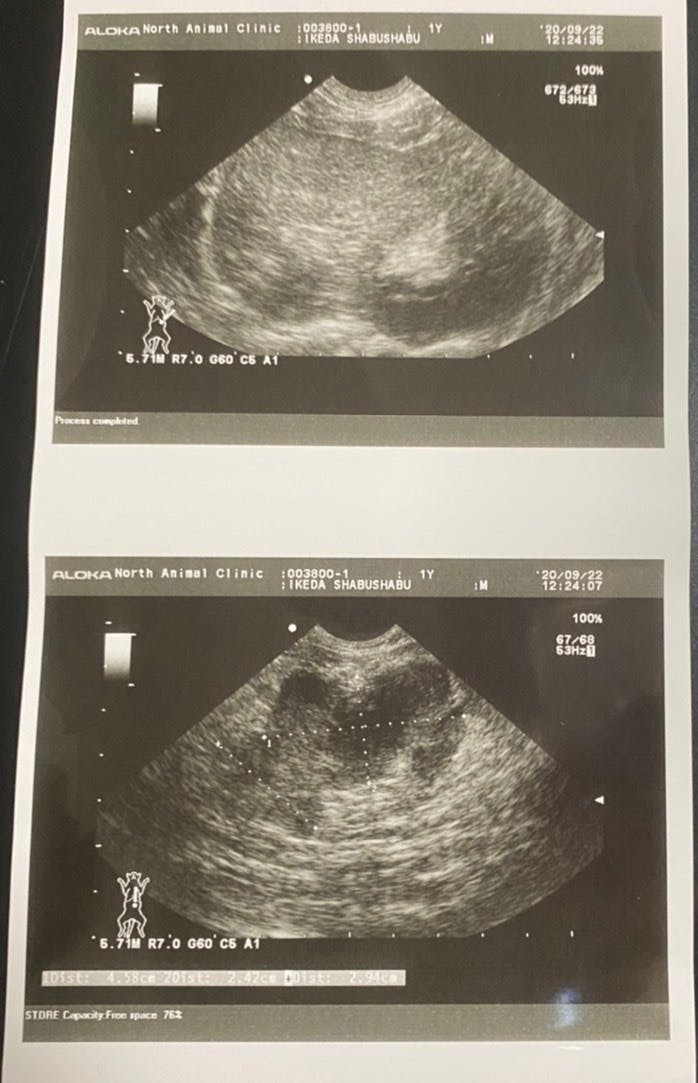

22日 未承認薬での治療のため違う病院へ。FIPドライタイプ 中期と診断。検査と7日分の未承認薬を購入222,970円 計 366,602円

(腹部に4cmの腫瘍が見つかりました。)

(血液検査の結果です。総ビルリビンとA/G比、白血球数の数値から、FIPと診断されました。)